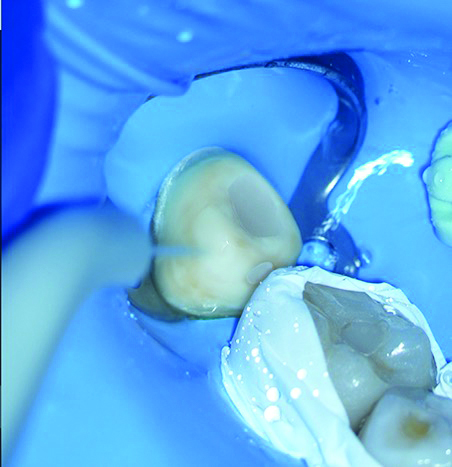

The final step of the clinical workflow involves complete isolation of the operative site using a rubber dam under the DOM to prevent contamination before cementation. After isolation was achieved the restoration was tried in to verify full seating, thus ensuring a precise marginal fit and tight proximal contacts, with smooth transitions and no overhangs (Figure 16).

Once the restoration fit was confirmed, the cementation process commenced by etching the tooth abutment with phosphoric acid while simultaneously protecting the adjacent tooth using Teflon tape (Figure 17). This was followed by rinsing and drying the abutment in accordance with the adhesive protocol (Figure 18).

Flowable dual-cure resin cement was applied to coat the intaglio surface of the restoration, with care taken to ensure minimal pooling, particularly near the margins. Light finger pressure was initially applied and gradually increased to achieve complete seating, allowing excess cement to escape. Dental tape was then passed through the proximal area, followed by an initial tack cure for 1 to 2 seconds to partially set the cement, thus stabilizing the restoration and facilitating the removal of excess cement.

Utilizing precise direct and indirect microscopic visualization, the clinician and assistant worked together to thoroughly clean the margins using an explorer. The dental tape was removed to prevent resin buildup between the interproximal contacts before the final light-curing was performed on all surfaces of the restoration for at least 20 seconds per surface using a high-power LED curing unit (Figure 19).

Fig 18. The tooth abutment was rinsed and dried.

Figure 18